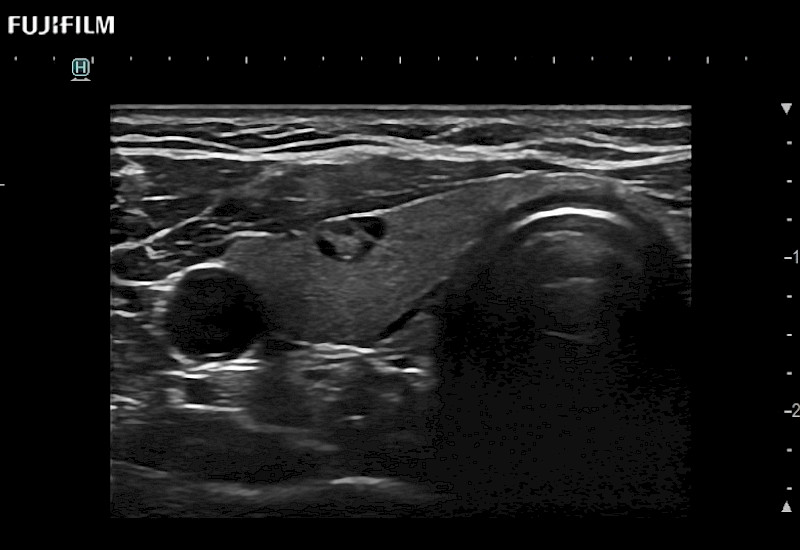

The ARIETTA 750 incorporates all of the proven technologies and functions that medical professionals have come to expect from Fujifilm Healthcare.

ARIETTA 750 is the definitive diagnostic ultrasound solution for any clinical setting - Private Office, Imaging Center, or Hospital. The ARIETTA platform provides the ultimate in clinical performance with its state-of-the-art features and large user-friendly display.

The ARIETTA 650 DI combines trusted Fujifilm Healthcare technologies and features tailored for surgical oncology.

Designed to meet the demands of surgeons, the ARIETTA 650 DI offers precise guidance. Its advanced capabilities and large, intuitive display offer accurate and efficient care in operating rooms and specialized surgical settings.